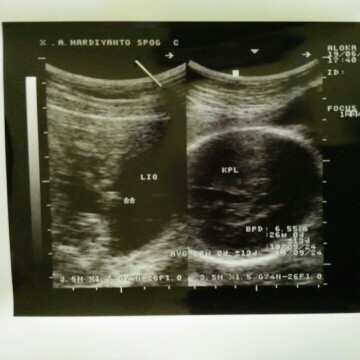

USG di 26 minggu

Baca lagiKPL itu mungkin maksudnya kepala, bun. Saya beberapa kali hasil yang di foto bagian kepala atau perutnya, Bun. Kalau saya biasanya nanya berapa beratnya dan gimana ketuban. Dua minggu lalu sempet melintang, jadi saya sujud aja, alhamdulillah kemarin udah di bawah kepalanya.

Susah bun klo cm gambar gt doang. Yang pasti sebelah kanan itu gambar kepala bayi dri atas. Dokternya ga ad nyatet beratnya jg di gambar.. cm dokternya aja yang tau bb berapa panjang brp deh :v.. paling ada distatus rs. Ibu lain kali nanya mendetail..

ku cuma bisa liat sedikit2... krn samar bgt tulisannya... yg KPL itu kepala bun BPD 6,55 cm (itu ukuran diameter kepala) 26 w 0 d (usia kehamilan) ga ada keterangan berat janinnya bun, (atau aku yg ga kebaca)